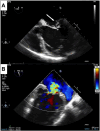

A 53-year-old male individual with chronic severe mitral regurgitation presented with biventricular dysfunction, pulmonary hypertension, and atrial fibrillation. Echocardiography demonstrated a posterior leaflet prolapse with malcoaptation. Mitral valve repair and Maze procedure were performed, revealing absent chordae and direct connection from the anterolateral papillary muscle to the posterior leaflet, consistent with partial mitral arcade. Post bypass, left ventricular dysfunction was addressed by intraaortic balloon pump placement and delayed sternal closure. Post chest closure echocardiography showed no residual mitral regurgitation and restored biventricular function. This case highlights a rare presentation of mitral regurgitation with unique anatomical anomaly, successfully managed with a comprehensive surgical approach.